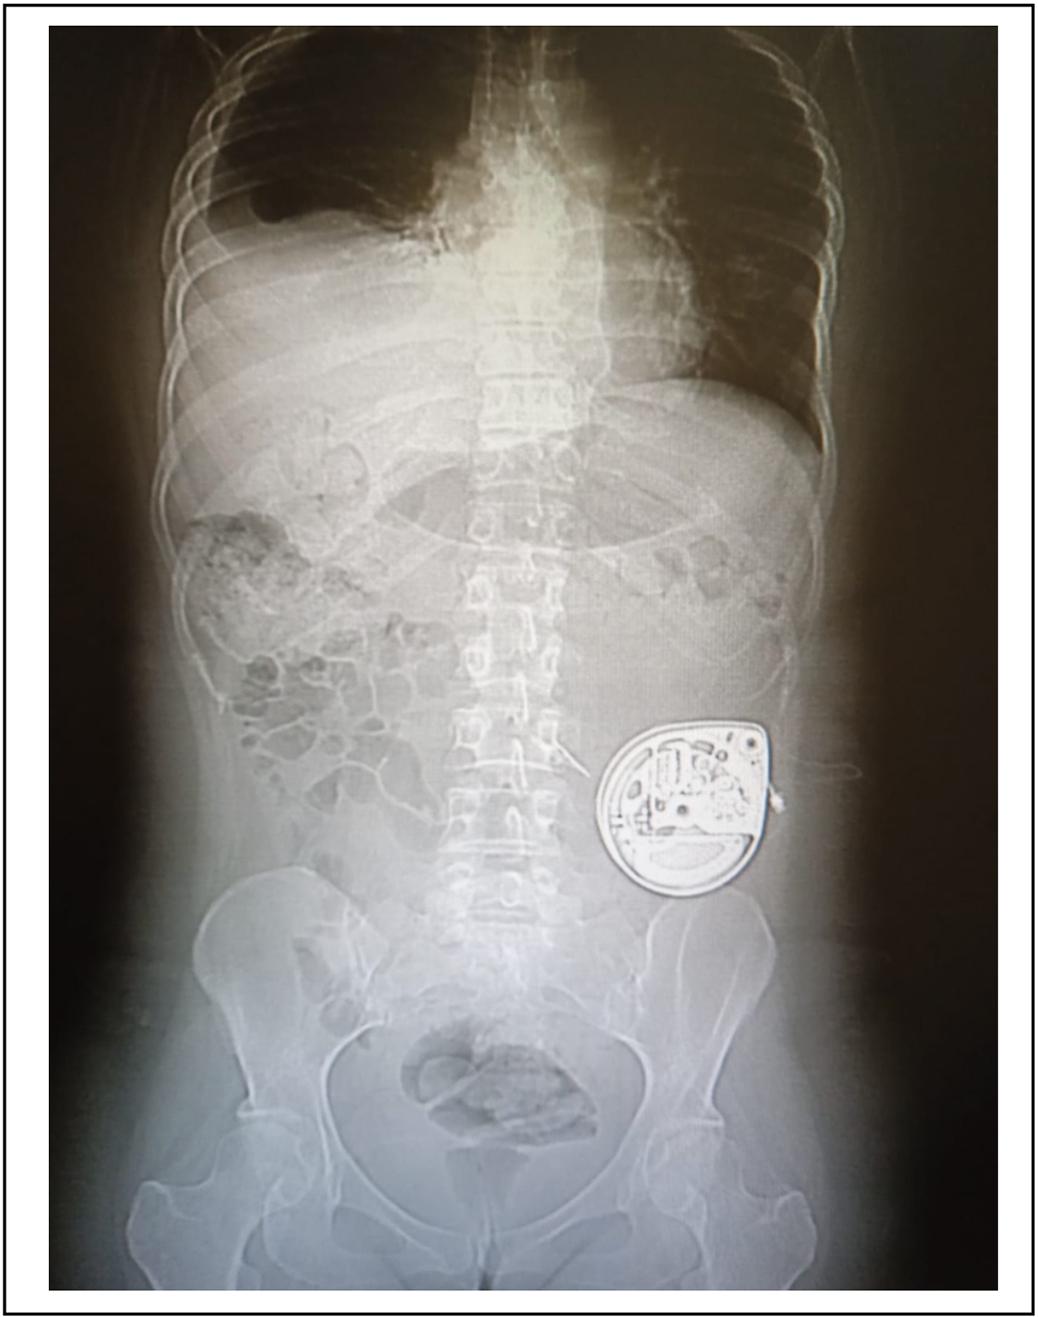

En el día 2 se administra bolo de 1.000 μg de morfina IT, con respuesta positiva (disminución del dolor mayor al 50%) y mejoría de estado funcional, logrando deambular con dolor leve (EVA 3/10). Como EA de esta dosis, se registra sedación leve según la escala de toxicidad de la OMS (1: leve, 2: moderado, 3: severo, 4: amenazante para la vida). Se procedió al implante del catéter intratecal por punción percutánea a nivel del espacio interespinoso L1-L2 llevando su punta hasta un nivel superior torácico (T8-T9). El otro extremo se conectó en forma subcutánea a la bomba programable electrónica (Bomba de Infusión Programable Synchromed Medtronic) que se alojó en un bolsillo subcutáneo abdominal. (Figura 1).

Figura 1. Bomba programable colocada en el espesor del celular subcutáneo de la fosa ilíaca izquierda.